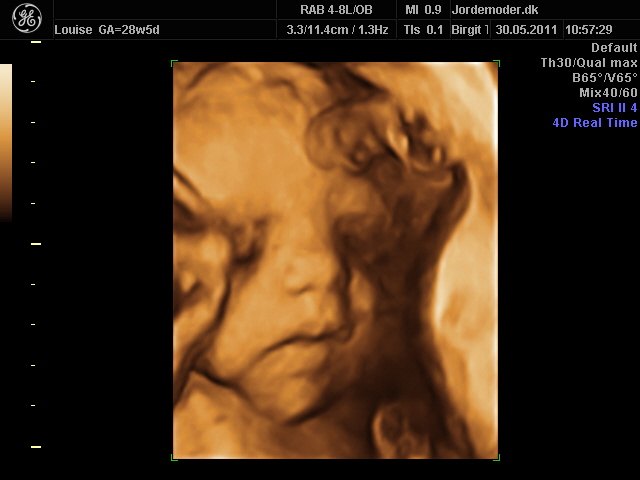

Så kom vi til 3d scanning igår. Lillepigen er slet ikke så stor som egen Jm kønnede hende HELDIGVIS! 1500 gram ca vejer hun nu, 28+6....

Hun har den fineste mund, jeg er helt misundelig på de smukker læber hun har.¨Ja hun er jo alt i alt bare dejlig, og jeg har ikke engang set hende sådan helt rigtig endnu.... Også har hun nogen gode runde kinder....

I skal ikke snydes for billeder af vores lille skønhed...